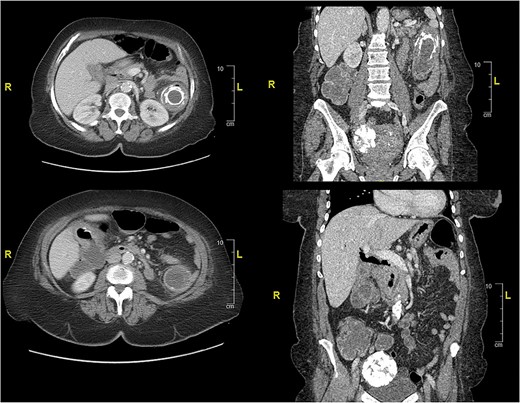

Case presentation #2: A 39-year-old male initially presented with acute cholecystitis (AC) with a markedly thickened wall with abscess formation, not amenable for drainage, treated with antibiotics with improvement, but later experienced recurrent biliary colic symptoms. Repeat computed tomography (CT) imaging (Fig. 4) 2 months later showed a peripherally hyperdense septated collection within the porta hepatis with surrounding fluid signal attenuation; likely representing an abscess seen around the gallbladder possibly secondary to gallbladder perforation due to neoplastic versus inflammatory pathology. Ultrasound showed chronic cholecystitis with cholelithiasis. The patient later underwent elective laparoscopic cholecystectomy. Intraoperatively, extensive adhesions from the liver to the gallbladder and the colon to the gallbladder were noted. The fundus of the gallbladder was densely adherent to the hepatic flexure with no dissection plane. The hepatic flexure felt firm, raising concern of a possible tumor or fistula. The decision was made to remove the right colon en-bloc with the gallbladder. The gallbladder was dissected free in the usual manner and a critical view was obtained. Once the gallbladder was freed, we proceeded with a laparoscopic right hemicolectomy with ileocolonic anastomosis. The specimen was evaluated on the back table; no tumor was seen, but there was what appeared to be an abscess cavity adherent between the gallbladder and colon filled with green stool-colored liquid. The patient tolerated the procedure well and was progressively advanced to regular diet postoperatively and discharged on postoperative Day 3. His final pathology of the operative specimen (Fig. 5) came back as acute on chronic cholecystitis with a micro-fistula between the gallbladder and the adjacent colon.

CT of abdomen and pelvis showing peripherally hyperdense septated collection within the porta hepatis with surrounding fluid signal attenuation likely representing an abscess seen around the gallbladder.